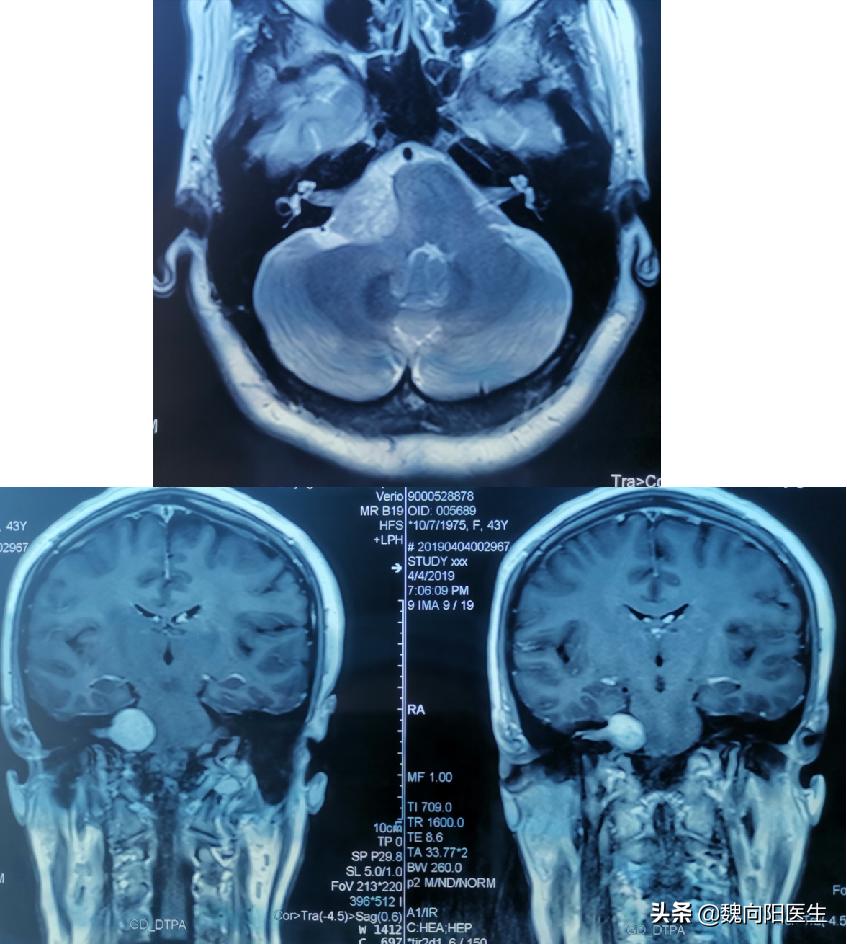

听神经瘤

耳鸣或发作性眩晕是最常见的症状,也是最初表现的症状,继而出现一侧听力减退,直至耳聋。

前庭功能障碍经常作为听神经瘤的早期表现为头晕/眩晕、不稳感。

三联征:耳鸣,眩晕和耳聋